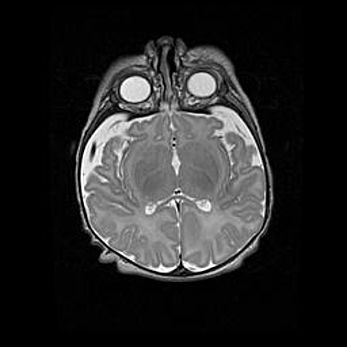

Лейкомаляция с кистозно-глиозной дегенерацией головного мозга.

Возраст: 2 месяца 25 дней

Вес: 6400 г

Окружность головы: 40 см

Срок гестации: 41 неделя

Лейкомаляцию относят к ишемически-гипоксическим повреждениям головного мозга, диагностируемым у новорожденных. При лейкомаляции в головном мозге обнаруживают очаги некроза, возникшие после тяжелой гипоксии и нарушения кровотока. В процессе морфогенеза очаги проходят три стадии: 1) развития некроза, 2) резорбции и 3) формирования глиозного рубца или кисты. Перивентрикулярная лейкомаляция (ПЛ) встречается примерно в 12% случаев среди новорожденных, обычно – у недоношенных детей, причем, частота ее зависит от массы, с которой младенец появился на свет. Наибольшее число малышей страдает лейкомаляцией, если масса при рождении 1500-2500 г.